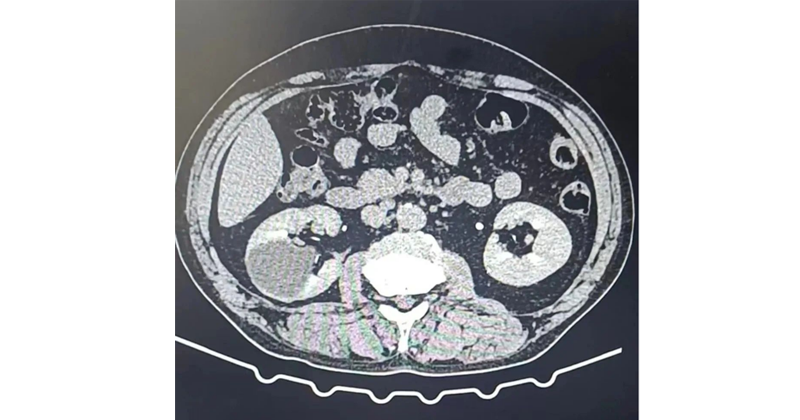

(2) CT對(duì)B超檢查不能確定者有價(jià)值。囊腫伴出血或感染時(shí),呈現(xiàn)不均質(zhì)性,CT值增加。當(dāng)CT顯示為囊腫特征時(shí),可不必再作診斷性穿刺。